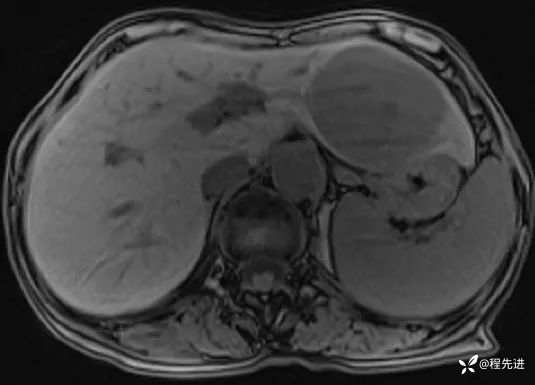

T2压脂: